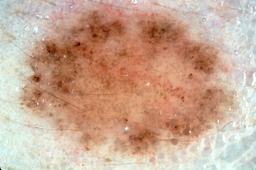

{

"age_approx": 25,

"anatom_site_general": "anterior torso",

"concomitant_biopsy": true,

"dermoscopic_type": "contact non-polarized",

"diagnosis_1": "Benign",

"diagnosis_2": "Benign melanocytic proliferations",

"diagnosis_3": "Nevus",

"diagnosis_4": "Nevus, Atypical, Dysplastic, or Clark",

"diagnosis_5": "Nevus, Dysplastic",

"diagnosis_confirm_type": "histopathology",

"image_type": "dermoscopic",

"lesion_id": "IL_6728561",

"melanocytic": true,

"patient_id": "IP_0913529",

"sex": "female"

}